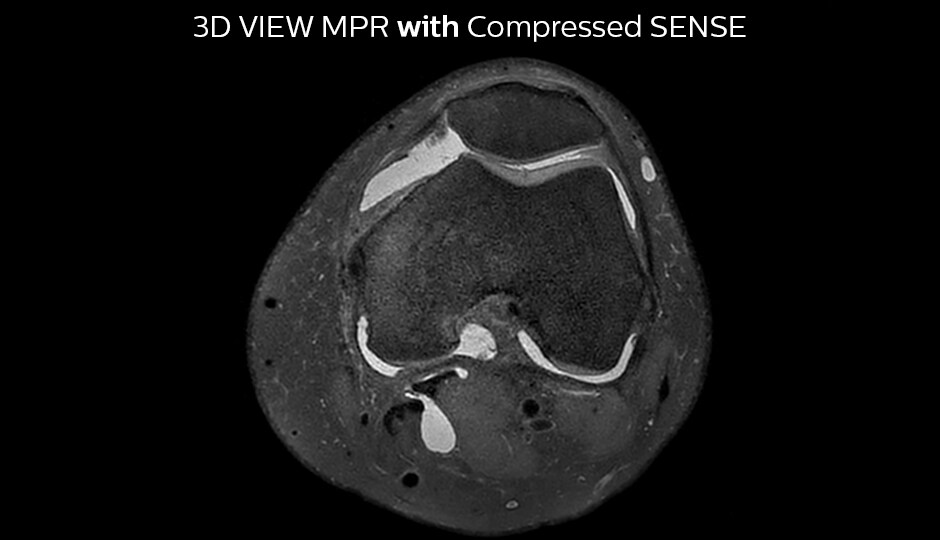

A good acquisition time with high resolution is obtained when moving from three 2D acquisitions in three planes to one 3D acquisition with Compressed SENSE. In this example, Compressed SENSE with 3D VIEW PD SPAIR is 50% faster than three separate 2D scans and has improved spatial resolution.

Without Compressed SENSE Scan time 2:55 + 3:37 + 3:51 = 10:23 min. Voxel size 0.55 x 0.65 x 3 mm

Three separate 2D PD scans in three orientations

With Compressed SENSE factor 10 Scan time 5:03 min. Voxel size 0.6 x 0.6 x 0.6 mm

3D VIEW PD SPAIR high resolution knee